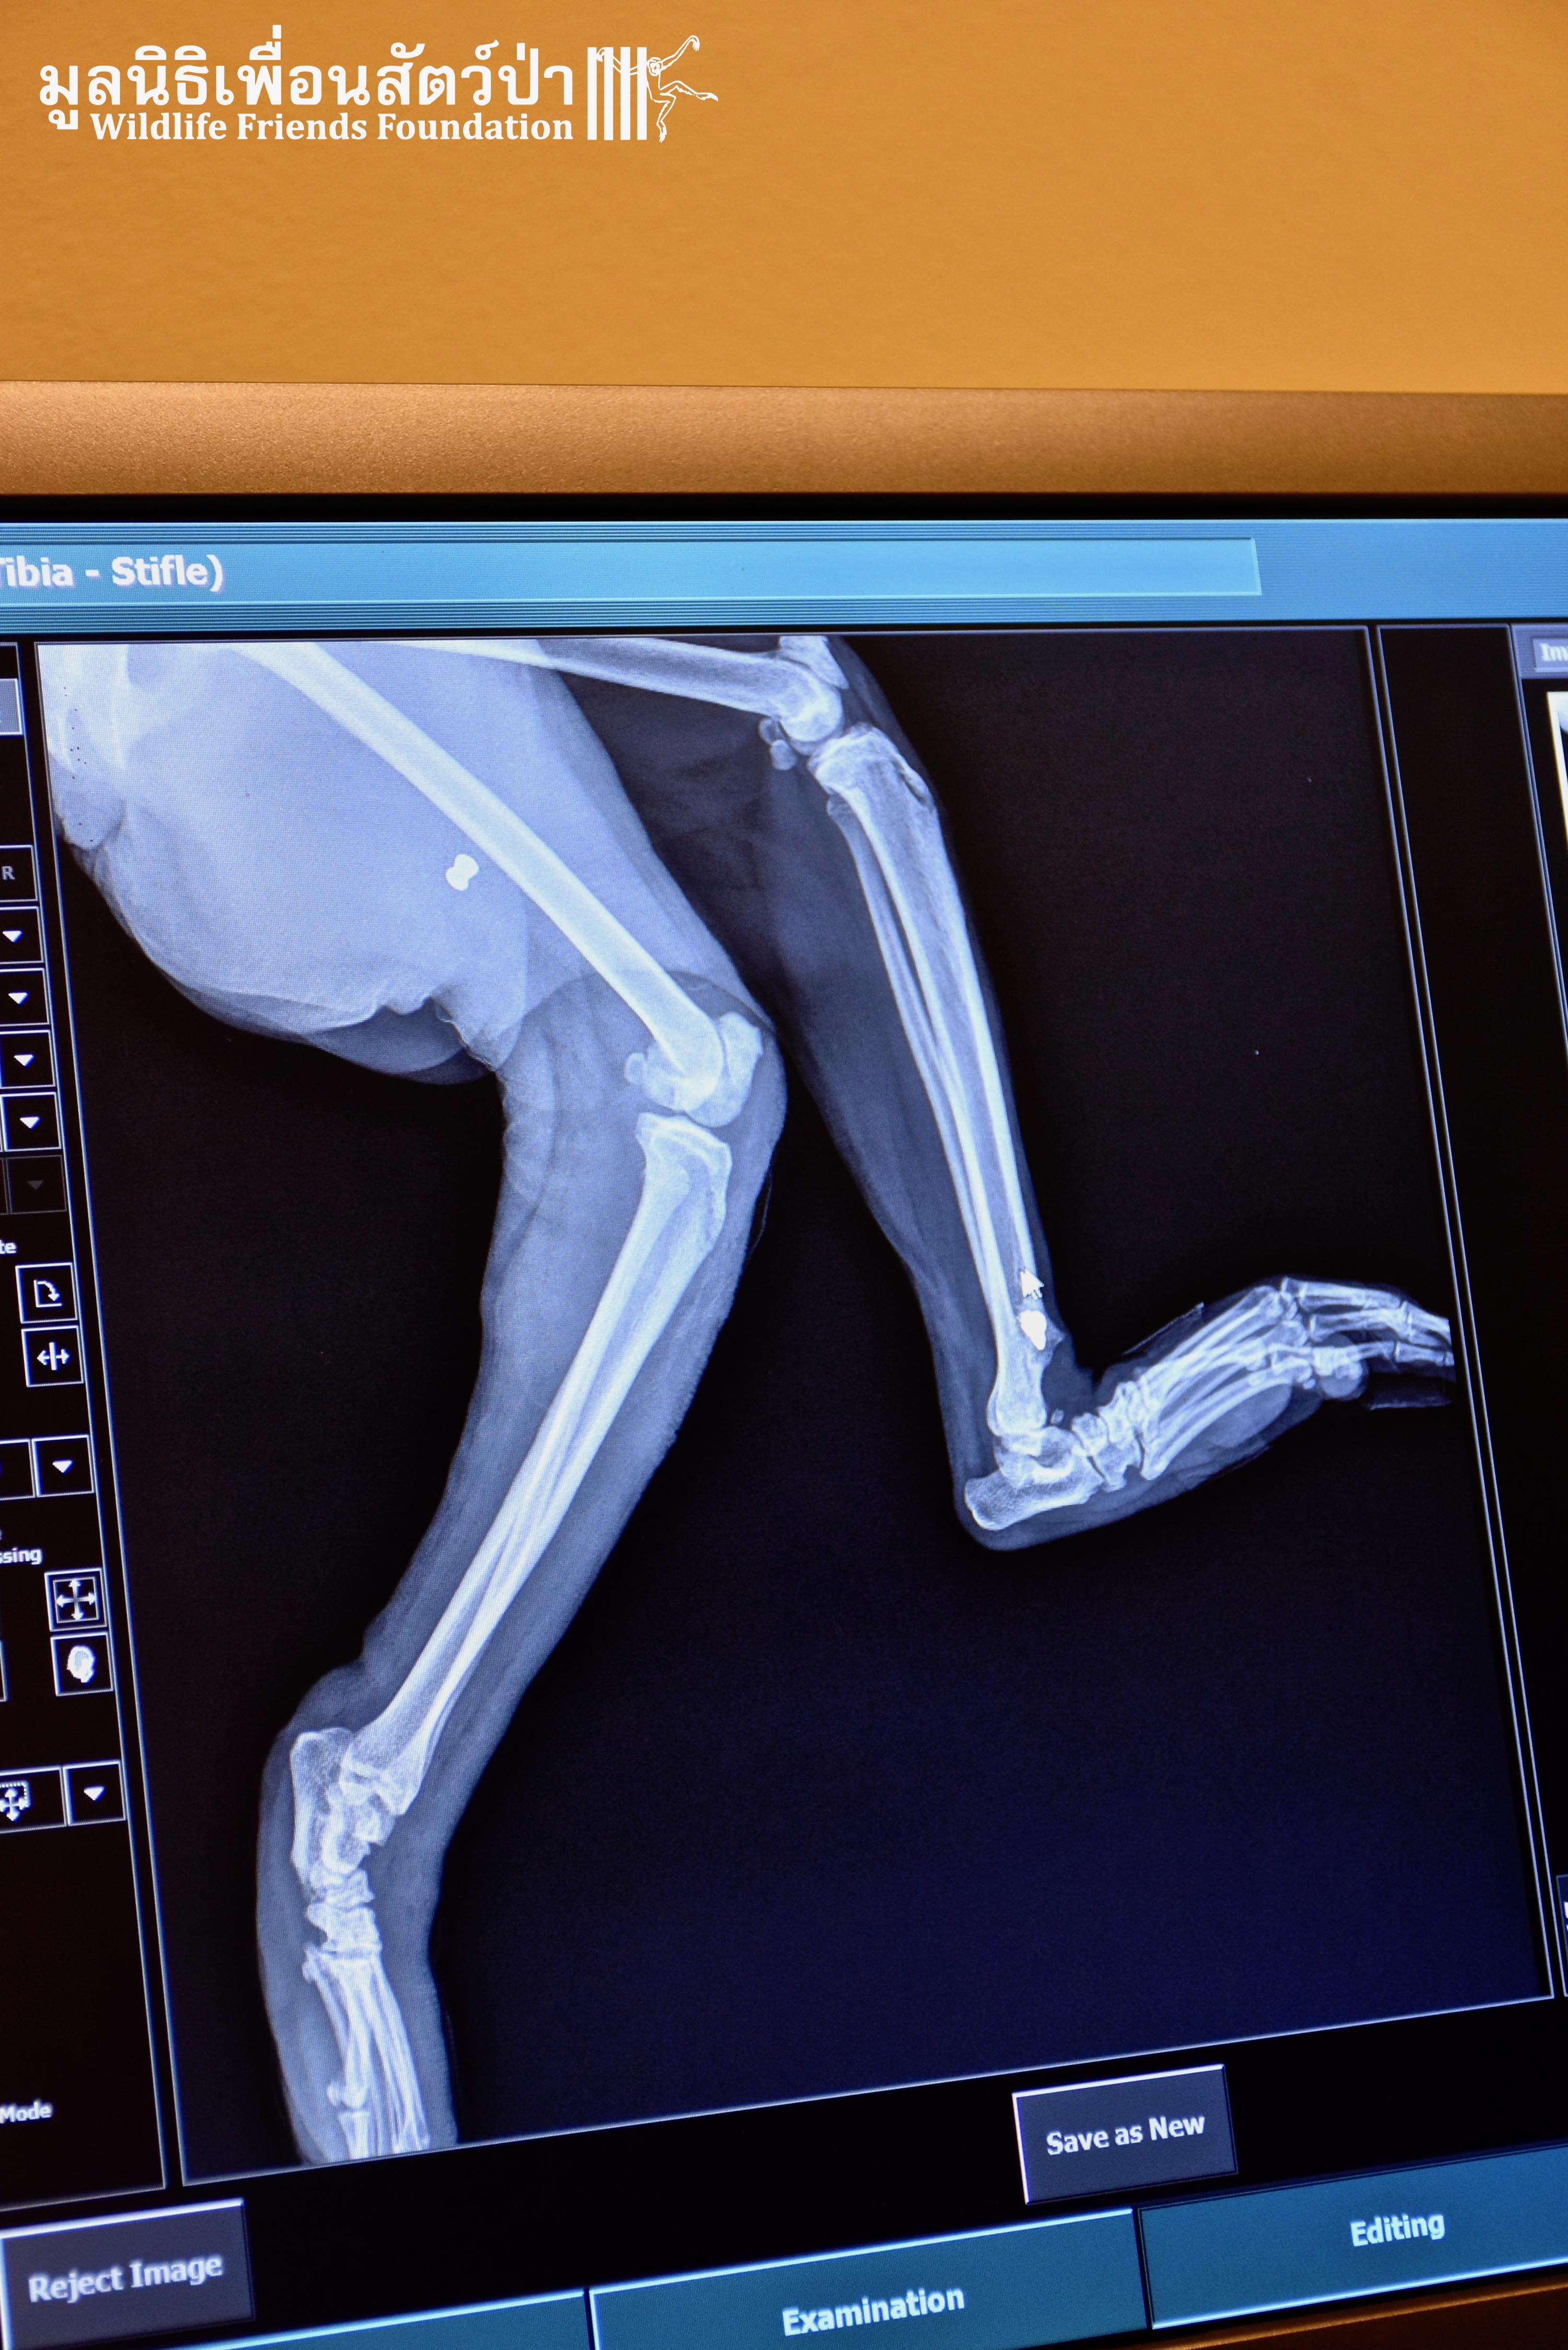

It was raining long-tailed macaques (Macaca fascicularis) in the hospital this week! Our first patient, Auan, arrived 2 months ago after being hit by a car. Although no breaks or dislocations were found, his radiographs revealed four old bullets lodged in his spine, thigh, ankle, and arm. His right leg suffered additional extensive abrasions from the car accident. Our hospital staff surmise that he has nerve damage that led to him painlessly dragging around his disabled limb, thus getting it infected. We decided to amputate this leg to avoid further complications. Because he is a large adult male, we are hopeful that he can be successfully released after he recovers and passes observation in quarantine.

Our second amputation of the day was of another long-tailed macaque, Bucky, who first came to us several months ago after falling out of a tree. He belongs to an urban macaque troop that is fed by a local community in Bangkok. They trapped and brought him to WFFT after noticing he had stopped using his arm. Once again, no breaks or dislocations were found in his radiographs but a fresh bullet wound was discovered in his disabled arm. It was removed and he was returned to his troop. However, he was brought back to WFFT this week because he still wasn’t using his arm. To avoid future risks of injury and sepsis, this arm was amputated after Auan’s leg amputation. After his recovery he will be returned to his troop in Bang Khun Thian, Bangkok.